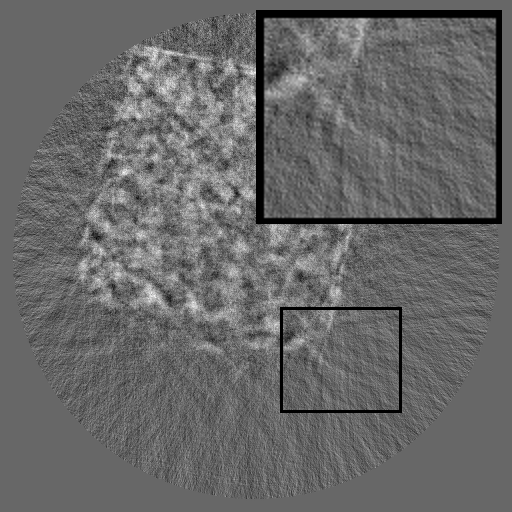

As shown in Fig 1, HiSin builds upon RePaint (Lugmayr et al., 2022) as its default backbone and restructures the inference process into a three-stage resolution-guided pipeline. The sinogram is first denoised at low resolution to establish global structure, then refined at mid resolution, and finally completed at full resolution through patch-wise inference. At each stage, the upsampled output from the previous resolution is fused with the current input before denoising, ensuring hierarchical guidance across scales. This hierarchical design avoids full-frame activation and substantially reduces memory usage while preserving long-range consistency. To further improve efficiency under the structural characteristics of sinograms, HiSin introduces two inference-time modules: (1) frequency-aware patch skipping, which exploits the spectral sparsity of background regions to bypass redundant computation, and (2) structure-adaptive step allocation, which leverages local structural heterogeneity to adjust denoising depth per patch.

Refer to caption

Figure 1: Overview of HiSin. The left illustrates the three-stage resolution-guided pipeline: low resolution followed by mid and high resolutions in a progressive refinement scheme, with the final stage performed patch-wise for detail recovery. At each stage, the upsampled output from the previous resolution is fused with the current input before denoising. The right zooms into the high-resolution stage, where two modules are applied: frequency-aware patch skipping (bypassing low-information patches) and structure-adaptive step allocation (assigning variable denoising steps by patch complexity).